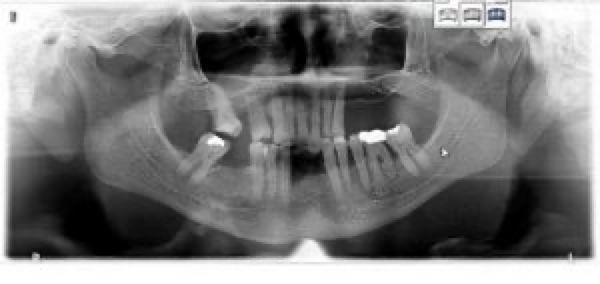

Parodontitis2

Ausgeprägter Knochenschwund des Oberkiefers bei seit vielen Jahren bestehender Zahnlosigkeit und flächiger Belastung durch die Oberkiefertotalprothese.